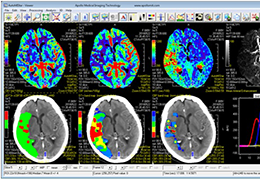

View X-Ray CT & MRI Scans Fast and Easily

Designed for surgeons, Pro Surgical 3D makes it easy to view patient scans quickly. Pro Surgical 3D facilitates the optimal 3D treatment and assessment workflows based on X-ray CT and MRI scans – and best of all, it’s FREE!

Traditional multi-planar slicing

High-quality and fast 3D reconstruction and 3D rendering

Multi-planar slicing.